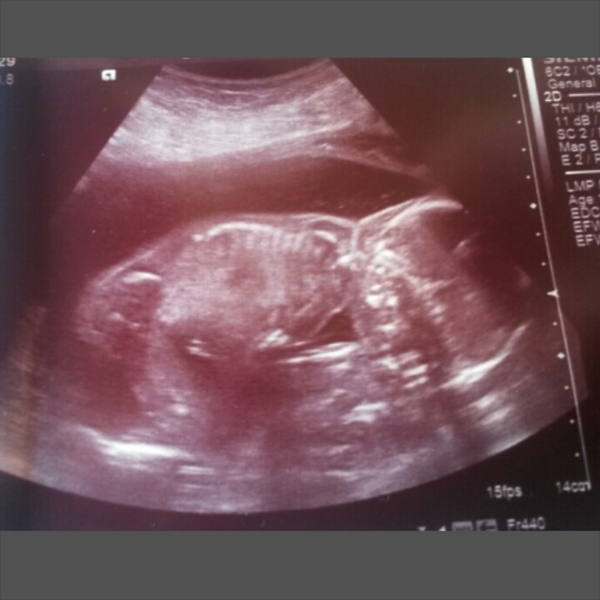

20 week scan today.

Started off pretty stressed as DH never received my "bring my notes" text so it was a mad dash across town for them!

Generally felt much more relaxed than 12 week scan though. Also I drank loads but peed about 15min before so was far more comfortable

Baby is healthy and happy and just how baby should be. Baby was hiding it's face in a corner and no amount of prodding or jiggling about would move it for the photo! So our scan pic has been named "The Faceplant"

And it's a GIRL :)

We are absolutely over the moon

19+5